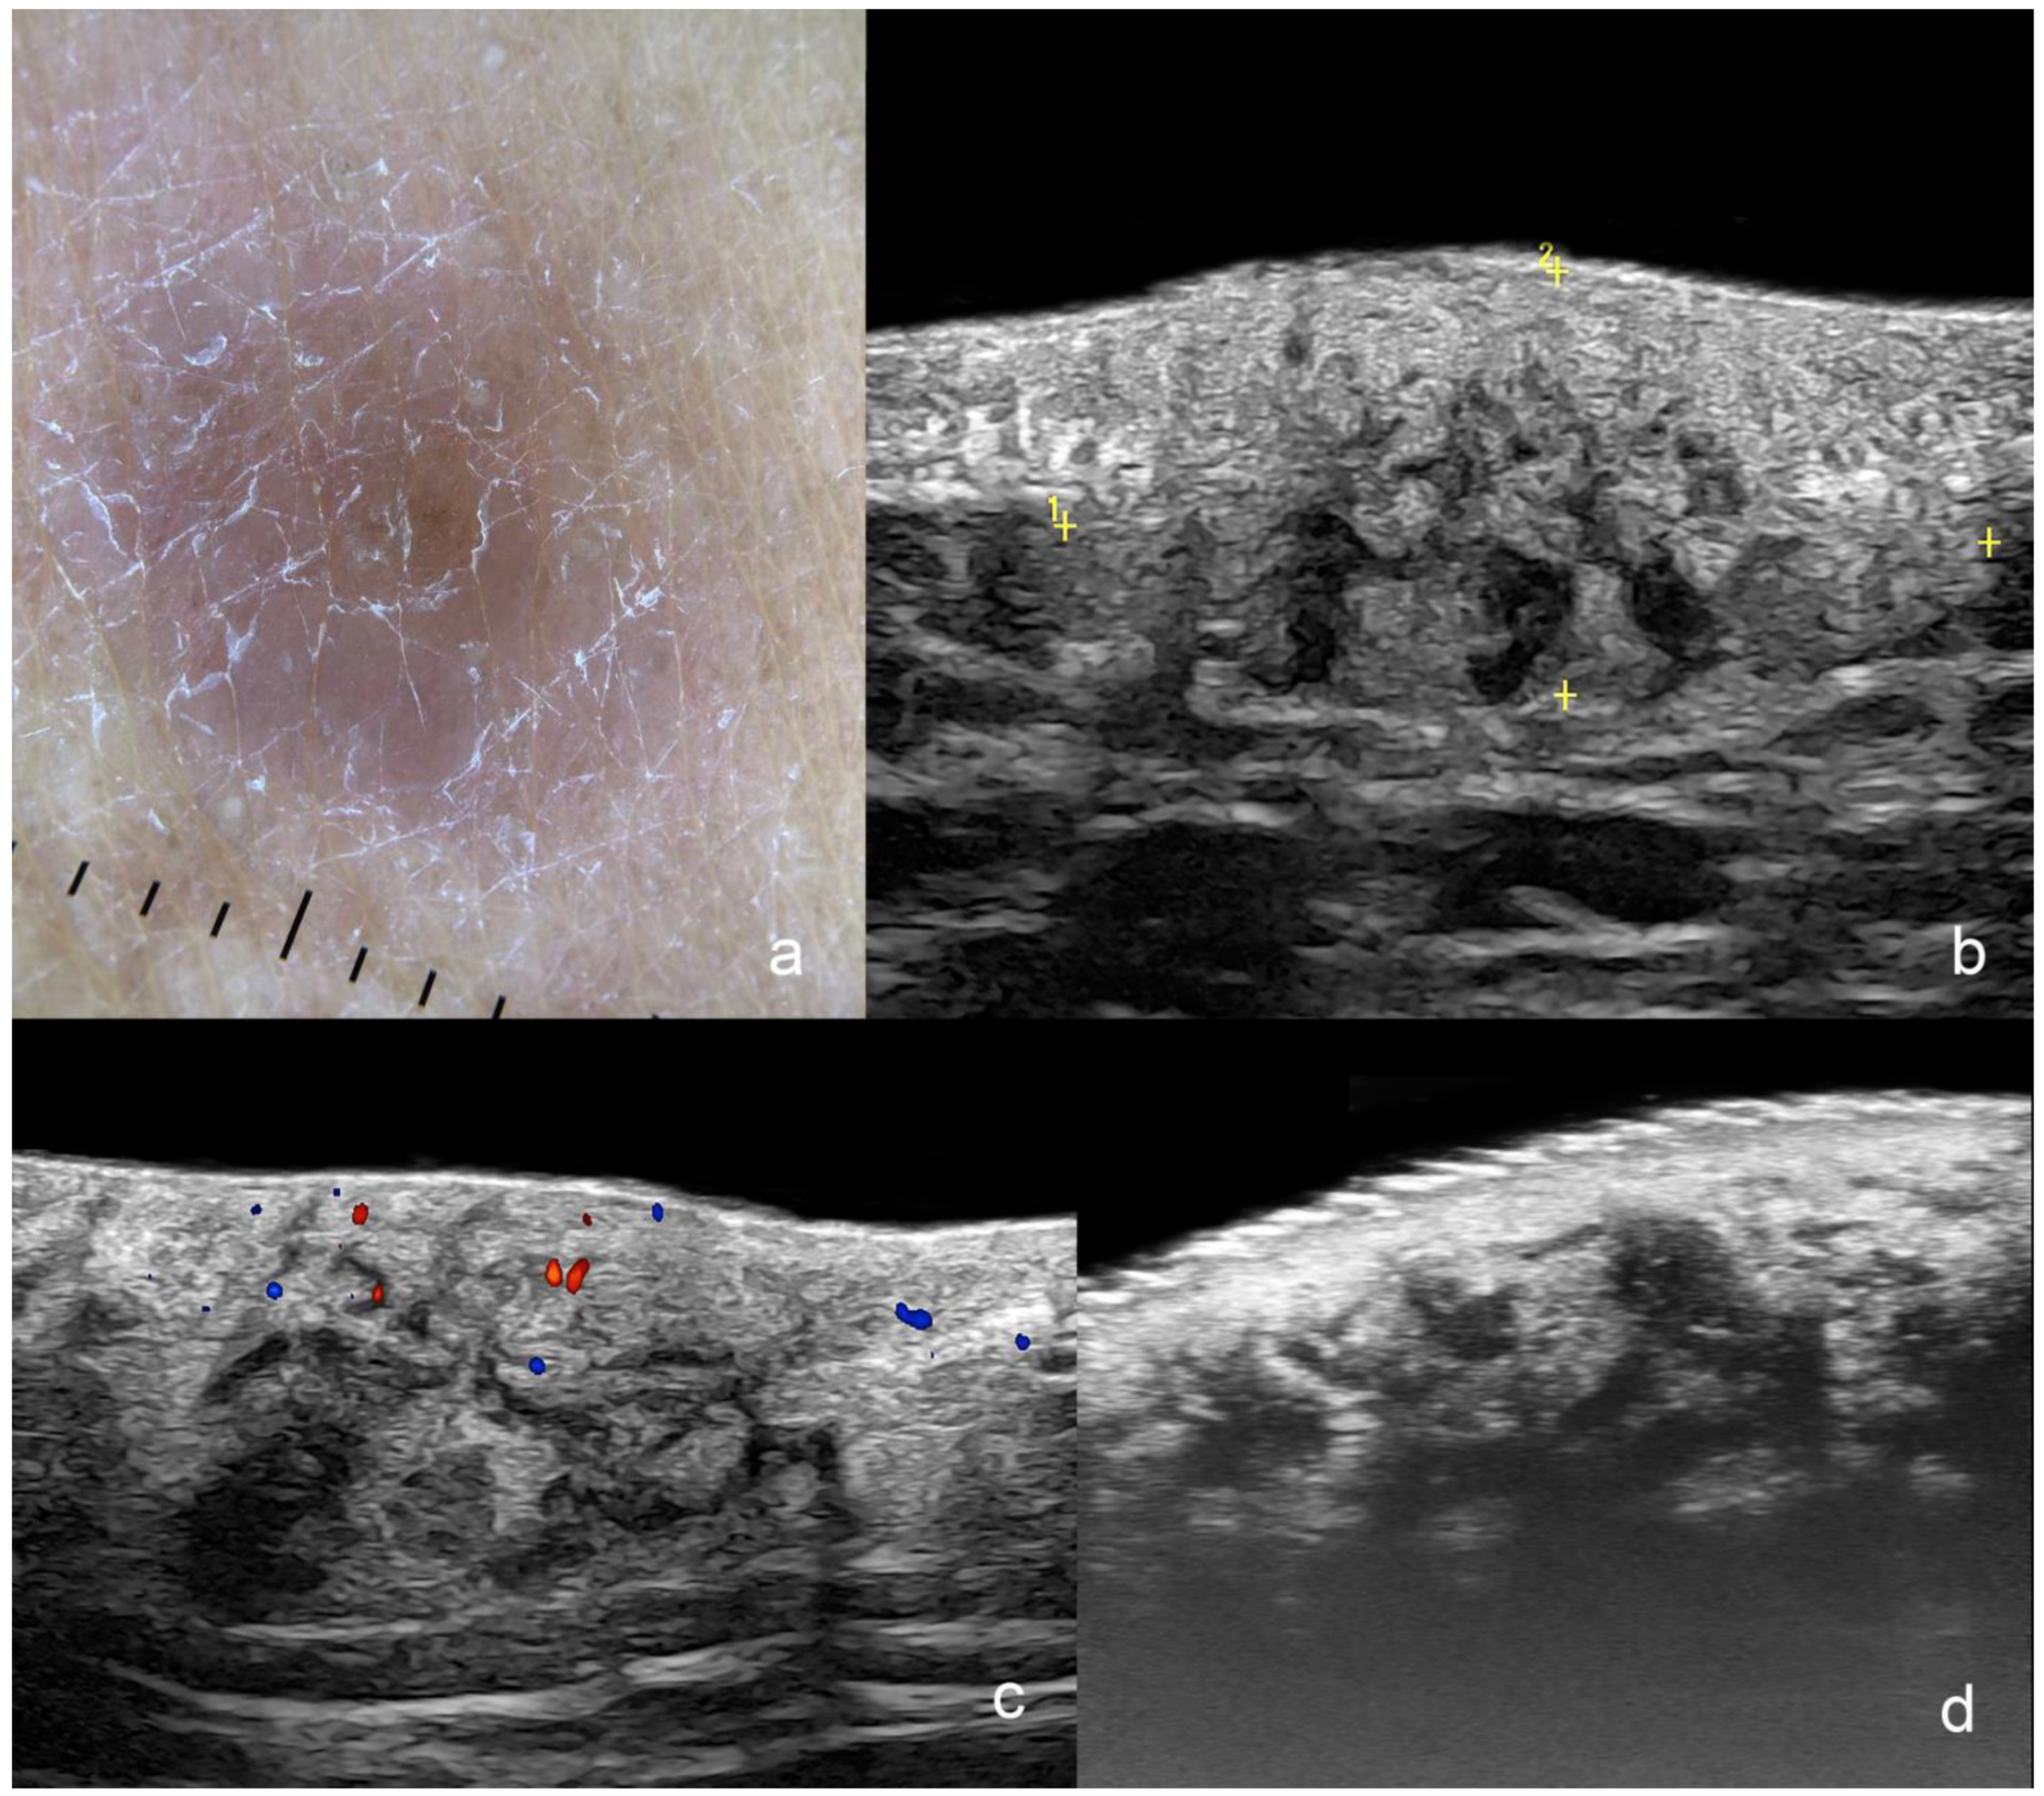

1.3.1. Basal Cell Carcinoma (BCC)

Primary BCC Tumor

| Basal Cell Carcinoma | hypoechoic, hyperechoic spots, oval, round, elongated, rosary-bead shape, variants with anechoic spaces, irregular borders | low degree |